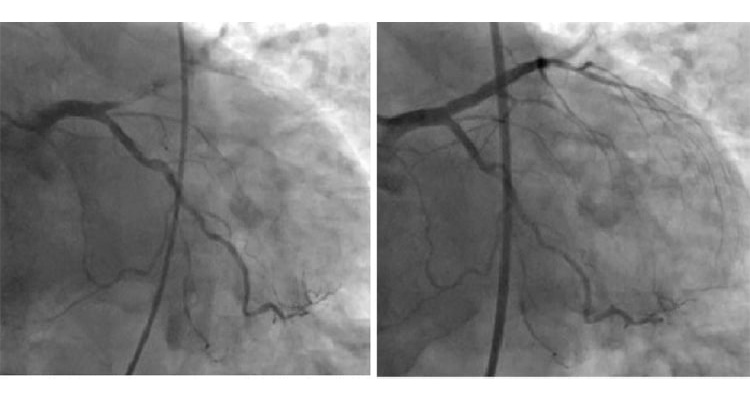

⑥冠動脈カテーテル検査

カテーテルという細長い管を手首や肘、足の付け根の動脈に通して心臓まで挿入し、造影剤を注射して冠動脈のX線撮影を行います。冠動脈の狭窄の程度、部位、病変数などを詳細に評価でき、冠動脈疾患を診断するのに最も正確な評価が出来る検査です。詰まって狭い箇所が見つかった場合は、引き続きカテーテル治療を行います。